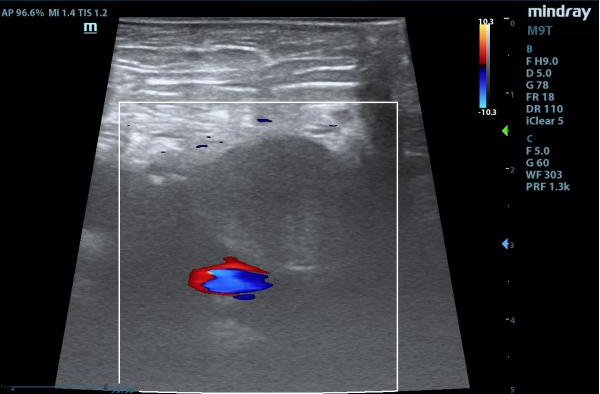

治疗后彩超(假性动脉瘤内无血彩,股动脉血流通畅)

术后24小时复查,B超提示患者假性动脉瘤栓塞良好。术后第七天再次复查彩超时,苏奶奶体内的瘤体已经完全被封堵,且股动脉血流通畅,无血栓形成。苏奶奶的病情得到了有效控制,治疗效果“立竿见影”。患者家属表示,原本他们对手术效果和费用都很担忧,但是朱晖副教授的精湛技术和团队的专业精神让他们感到非常放心和安心。